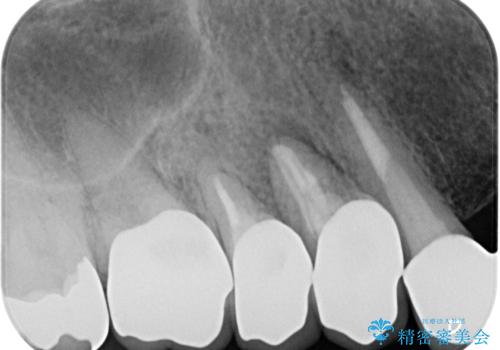

診察したところ、歯根に破折線が確認され抜歯が必要な状態でした。

歯肉や歯槽骨の状態は良好であったため、抜歯即時埋入インプラントによる補綴治療を行うこととしました。

膿の出口が認められた頬側の歯槽骨は欠損が大きかったものの、インプラント埋入には十分な骨があり、無事に短期間で治療を終えることができました。